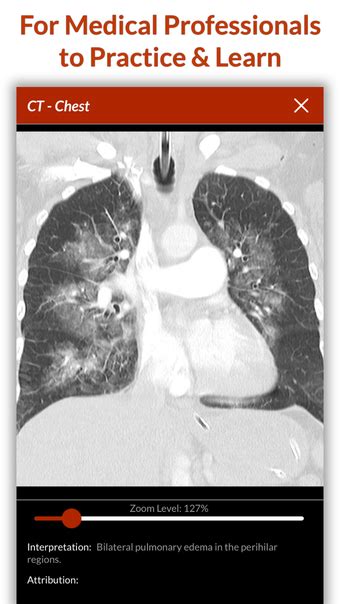

Full Code Medical Simulation by Full Code …

Full Code Medical Simul…

Full Code Medical Simulation on the App Store

Full Code Medical Simulation - APK Download for Android | Aptoide